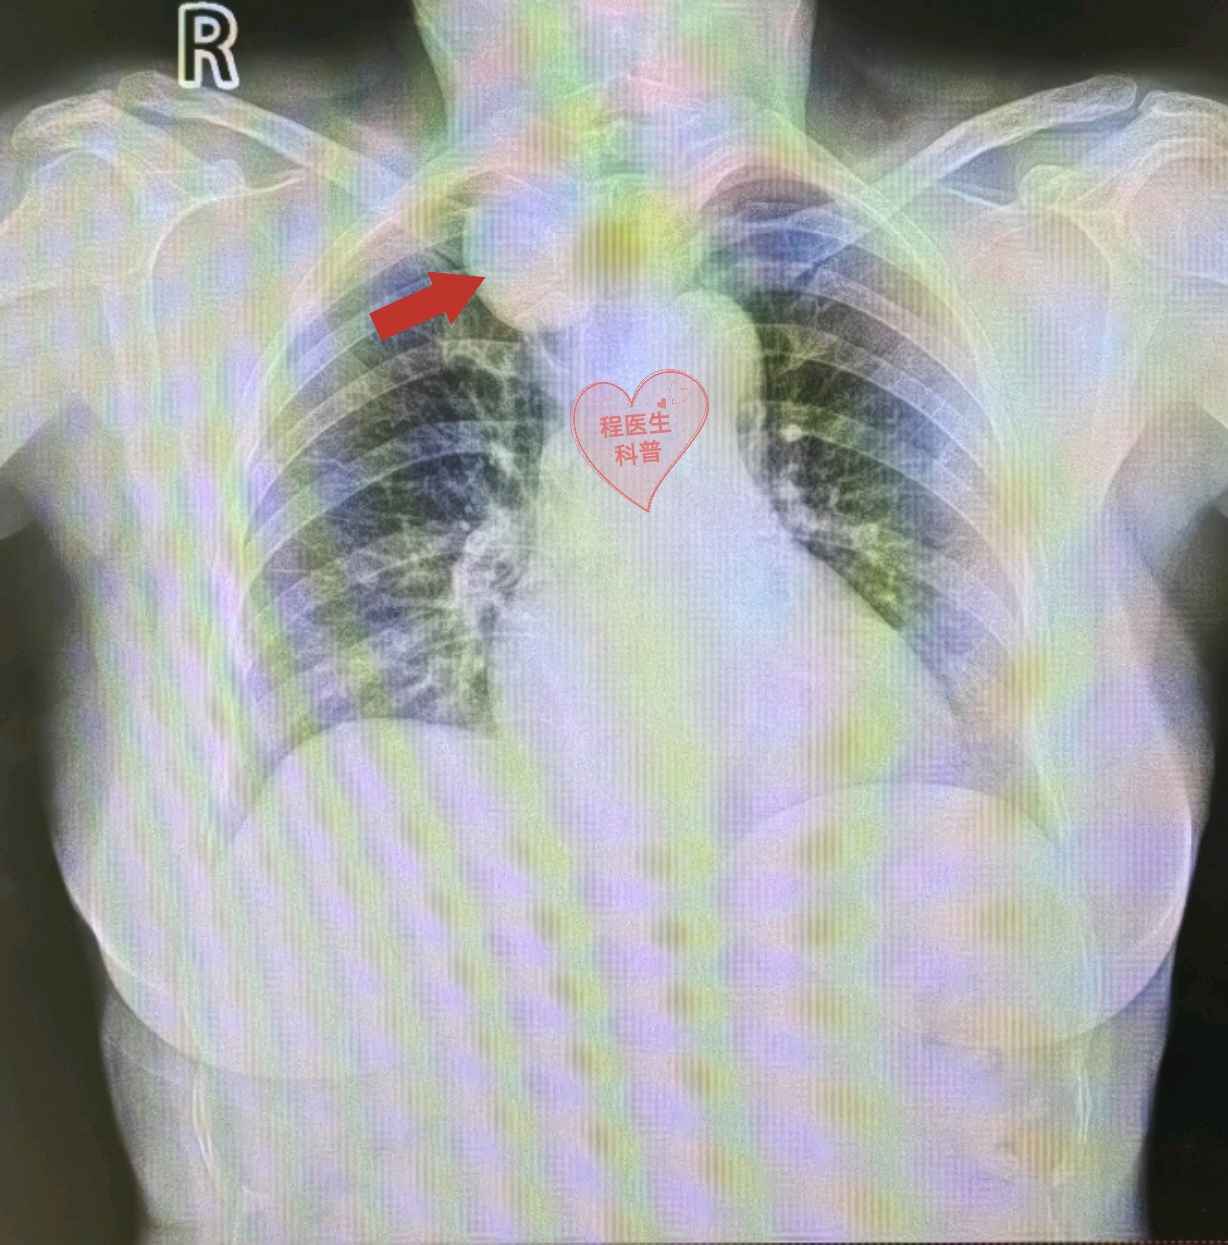

近日,秦大姐因公司体检,发现原来的瘤子长大了不小:以前CT才能看见的肿瘤这次居然被胸透发现了!为进一步了解病情,秦大姐利用工作间隙来我院进一步就诊。

通过胸部CT检查我们发现,秦大姐的肿瘤在一个关键的“交通要道”:大部分在胸腔,还有一小部分在颈部!此处既是神经的重要“聚集地”,也是血管进出上肢和头颈的必经之路,肿瘤继续生长可压迫血管、神经引起一系列并发症,严重者可能导致脑水肿、上肢功能障碍、视力障碍等问题,因此我们建议秦大姐早点手术治疗。